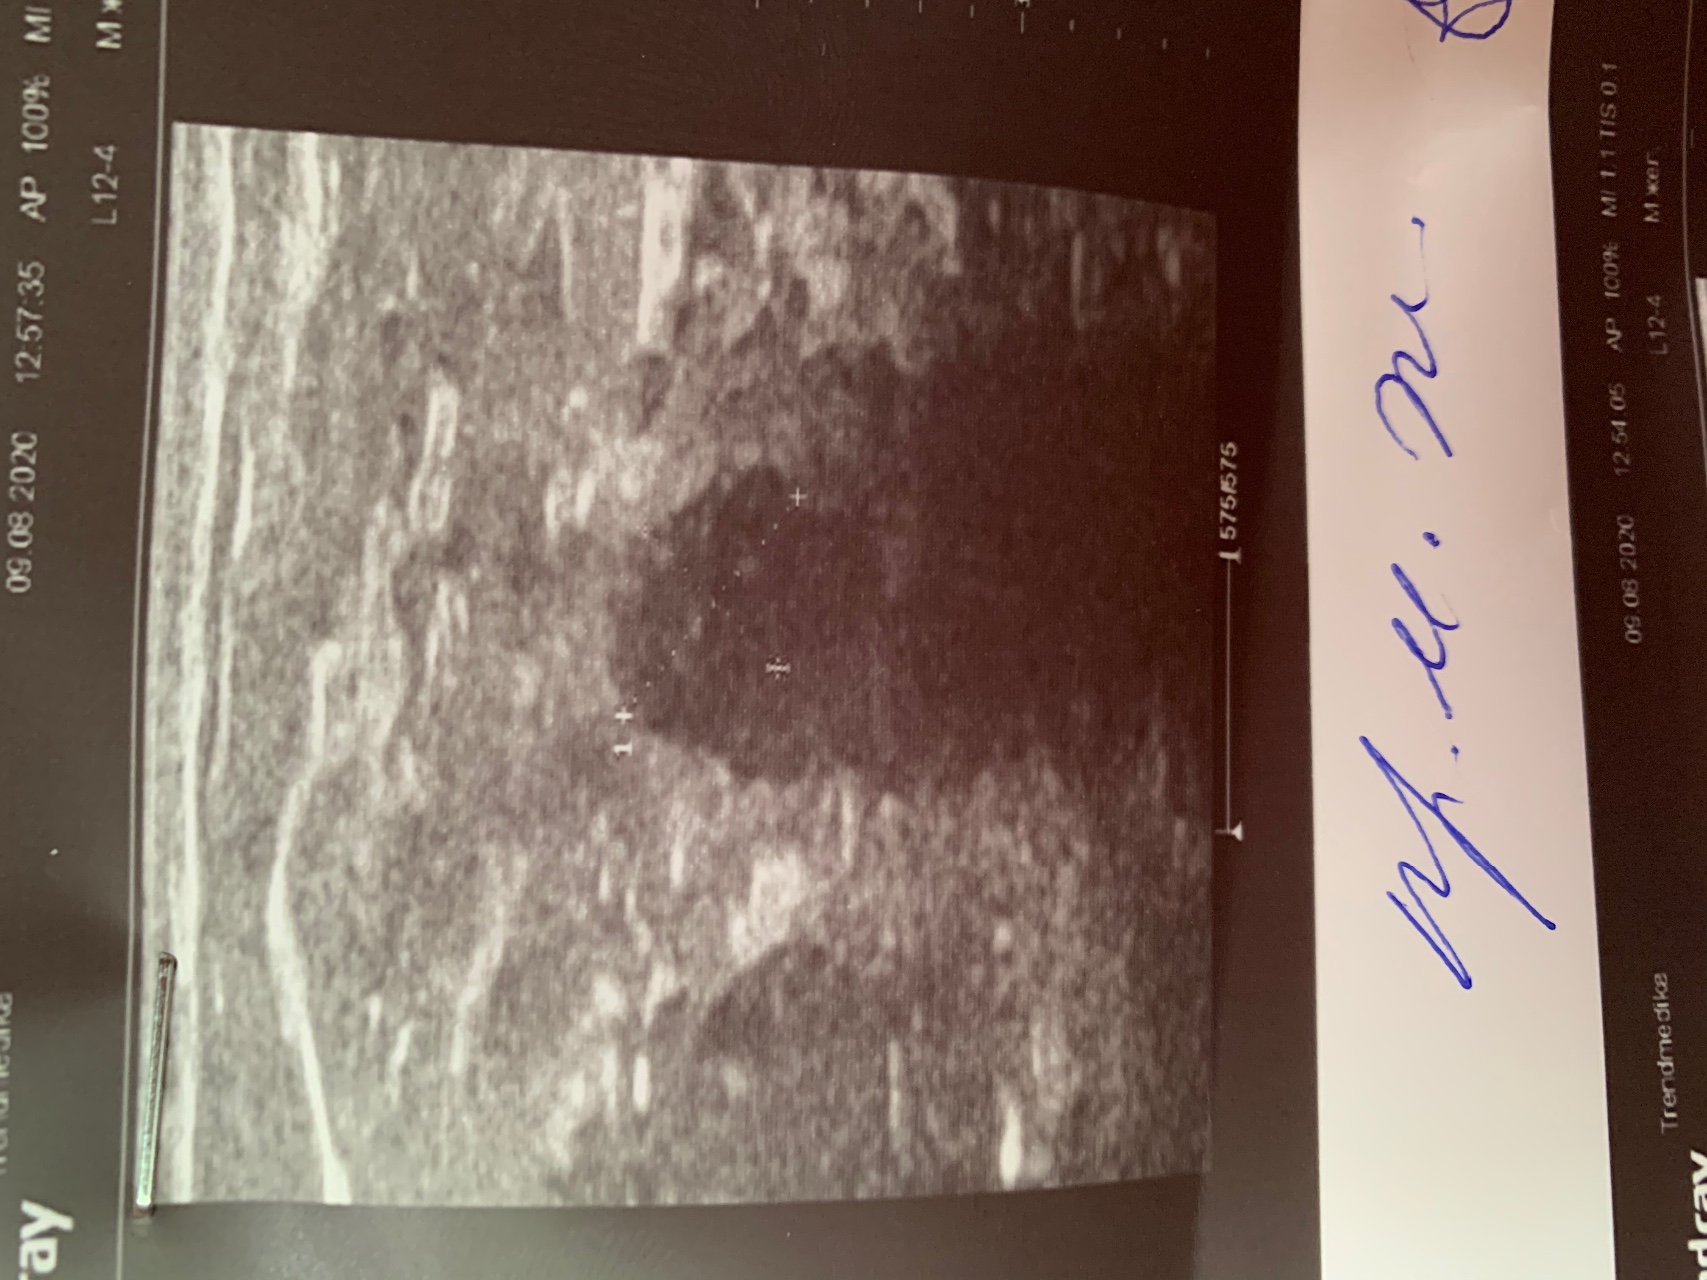

Фиброаденома молочной железы - доброкачественное образование, которое часто встречается у женщин. Оно может быть обнаружено при помощи различных методов диагностики, включая маммографию. Ниже представлены фотографии, помогающие понять, как выглядит данное заболевание.

Маммография и ее роль в диагностике фиброаденомы молочной железы

Маммография - это рентгенологическое исследование молочных желез. Оно позволяет выявить различные изменения в тканях, включая фиброаденому. На маммограммах можно увидеть структурные особенности опухоли и отследить ее динамику во времени.